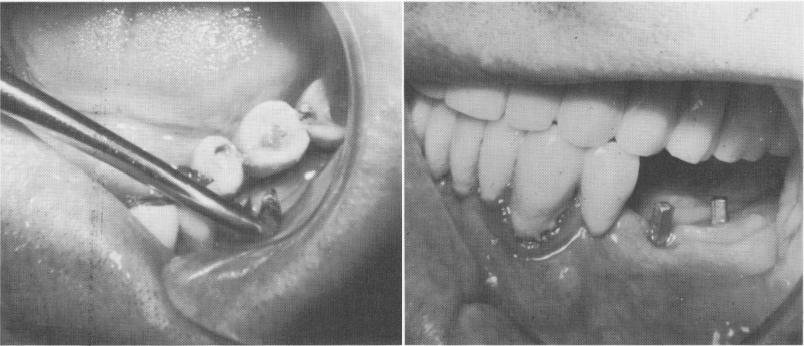

Fig. 4-47. The anterior implant was easily unscrewed. The posterior implants were removed by drilling out a circular core of bone surrounding each one. B, The removed implants. That on the right was so firmly embedded that it broke during removal.

1 View of vent plant endosseous implant posts in mandible

2 Circular core of bone drilled to remove posterior vent plant implants